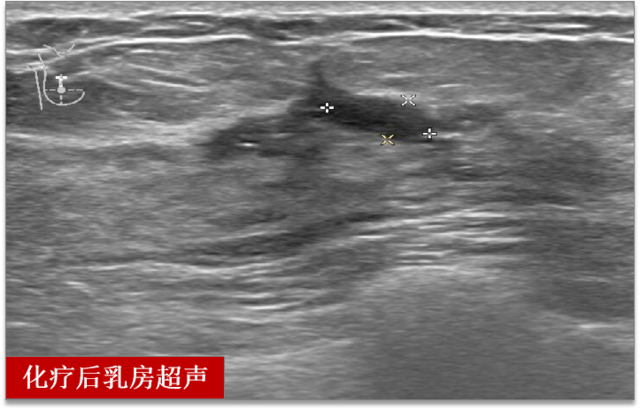

两个周期的化疗后

超声检查提示肝脏肿瘤完全消失

乳房肿瘤较前缩小